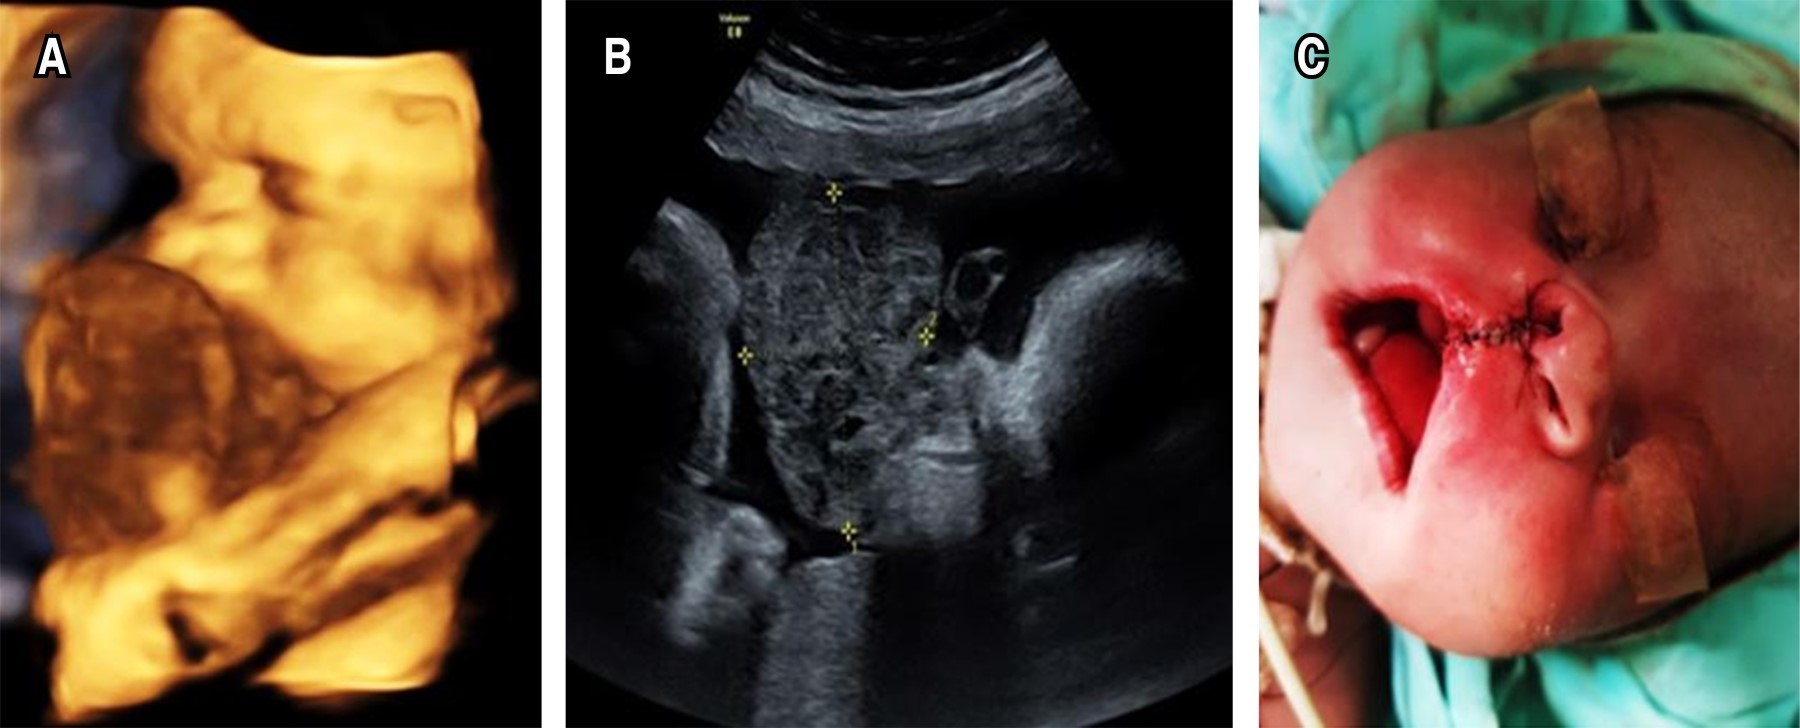

Recién nacido femenino de 39 semanas de gestación, peso de 2,040 gramos (< P3), talla 47 cm (P10), perímetro cefálico 33 cm (P10-50). Madre de 42 años, gesta 3. En ecografía prenatal a las 28 semanas de gestación se detectó tumor de predominio sólido, con áreas quísticas y de bordes irregulares, identificándose como epignathus (Figura 2A a C ).

El producto se obtiene por cesárea programada por técnica Ex Utero Intrapartum Treatment (EXIT). Inmediatamente al nacimiento, por dificultad para acceso a la vía aérea, se realizó traqueostomía con lo cual se logró estabilizar. En orofaringe, a nivel del paladar óseo, se observó una tumoración sólida e irregular, con dimensiones de 6 × 4 × 3 cm. También se identificó una hendidura en el paladar blando. Se procedió a realizar resección parcial y poteriormente pasa a UCIN.

A los 15 días de vida, se realiza resección en bloque de la tumoración completa y del paladar duro, sin dañar estructuras óseas circundantes, con colocación de sonda de gastrostomía para su alimentación. Se extubó al tercer día postoperatorio, sin complicaciones. Al quinto día postquirúrgico se inicia la alimentación en infusión continua, con adecuada tolerancia. Se egresa con alimentación por gastrostomía. Unas semanas más tarde la paciente desarrolla acumulación de líquido subdural bilateral, así como a nivel subgaleal del lado derecho, por lo que se coloca derivación peritoneal subdural, sin complicaciones.

El reporte del estudio histopatológico fue de teratoma maduro. Con respecto a los niveles de AFP, antes de la cirugía fueron de 39.5 ng/mL y, posteriormente disminuyeron a 26.2 ng/mL, 8.6 ng/mL y 4.9 ng/mL al mes, seis meses y al año del postquirúrgico.

Al tercer mes de vida, la succión mostraba mejoría, ya que en los primeros dos meses del postoperatorio estaba disminuida, requiriendo ejercicios de rehabilitación. A los seis meses de edad, el desarrollo motor grueso era normal.